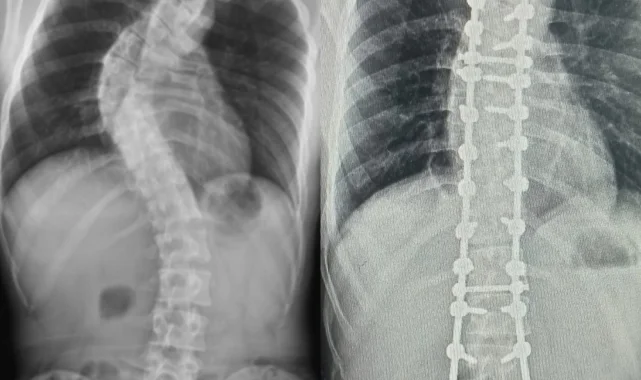

Yapılan muayene ve incelemeler sonucu hastada 73 derece skolyoz (omurga eğriliği) ve kifoz (kamburluk) tespit edilerek Ahmet Akan'a ameliyat önerildi. Samsun Üniversitesi Tıp Fakültesi Ortopedi ve Travmatoloji Anabilim Dalı Öğretim Üyelerinden Dr. Öğr. Üyesi Ömer Bozduman, deneyimli ameliyat ve anestezi ekibi eşliğinde görev yaptığı Samsun Eğitim ve Araştırma Hastanesi'nde 7 saat süren başarılı bir skolyoz ameliyatı gerçekleştirdi.

Hasta ile ilgili bilgi veren Dr. Öğretim Üyesi Ömer Bozduman, "Hastamız artan sırt ağrıları ve omurga eğriliğinin ilerlemesi şikâyetiyle kliniğimize başvurdu. İnceleme ve değerlendirmelerimiz sonucu ameliyat kararı verdik. 7 saat süren skolyoz ameliyatını takiben 12 saat sonra hastamız kaldırılıp yürütüldü. Ameliyat sonrası nörolojik olarak hiçbir sorunu yok. Eğriliği tamamen düzeldi, boyu uzadı. Şu an kendisi yürüyüp gezebiliyor. Hastayı 5 gün sonra taburcu edip evine gönderiyoruz. Her ameliyatta olduğu gibi skolyoz ameliyatlarında da ekip çalışması çok önemlidir. Uzun süren bu ameliyatı, hastanemizin özverili ameliyat ve servis hemşireleri ve deneyimli anestezi ekibi ile gerçekleştirdik" dedi.